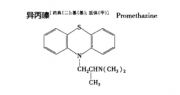

| 2021年7月26日 (一) 20:03 | 异丙嗪结构式.jpg (文件) |  |

17 KB | Uploaded with SimpleBatchUpload | 3 |